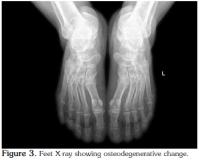

The patient was then admitted for further investigation. From an analytical point of view, there was an increase in acute phase reactants [C-reactive protein (CRP) 95.2 mg/L and erythrocyte sedimentation rate (ESR) 87 mm/hr]. Microcytic anemia was also present (hemoglobin 11.2 g/dL, mean erythrocyte volume 79.4 fl, and iron 37 mg/dl), but the ferritin and serum levels were normal as were the total iron binding capacity and transferrin saturation rate. Serum protein electrophoresis revealed a decrease in albumin (47.3%), whereas the alpha 1 (16.1%), alpha 2 (14.9%), and gamma globulin (21.3%) levels were higher. Other immunological tests determined that the rheumatoid factor (RF), anticyclic citrullinated peptide (anti-CCP), antinuclear antibody (ANA), complement, and anti-doublestranded deoxyribonucleic acid (anti-dsDNA) levels were normal, and the serum uric acid levels were also within normal limits. Furthermore, the primary and secondary tuberculosis screening tests were negative, and the serology tests for Brucella, Chlamydia, the human immunodeficiency virus (HIV), and hepatitis B and C were negative as well. Human leukocyte antigen typing revealed the presence of A1, A2, B41, B57, Cw6/7, DR11, and DR13 while a urinary system ultrasound and an intravenous pyelogram were normal. An X-ray of the pelvis showed degenerative changes (Figure 1), and because of the patient's ongoing lower back pain and peripheral joint swelling, magnetic resonance imaging (MRI) of the sacroiliac joints was performed, which showed periarticular edema of the sacrum in the anterior segment along with a slight increase in sclerosis of the right sacroiliac joint in the anterior superior segment. Slight edema of the left periarticular sacral area was also seen in the posterior segment. We then recommended that the MRI findings be interpreted in accordance with the clinical picture.